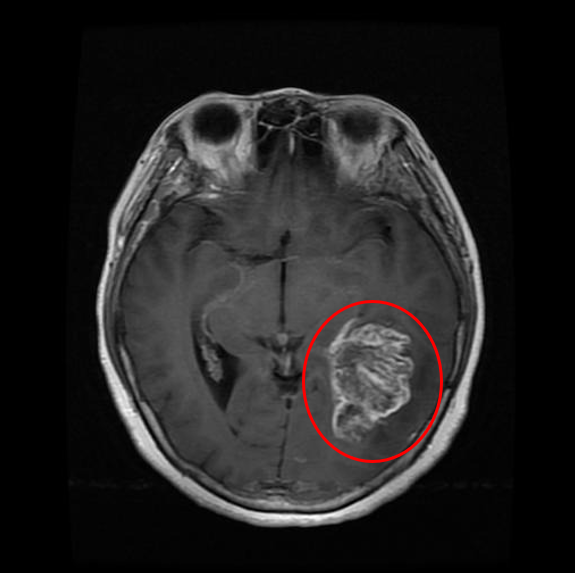

Glioma is a type of tumor that occurs in the brain and spinal cord. Gliomas begin in the gluey supportive cells (glial cells) that surround nerve cells and help them function. Three types of glial cells can produce tumors. The circled red part on the right side of the brain is the Glioma tumor.